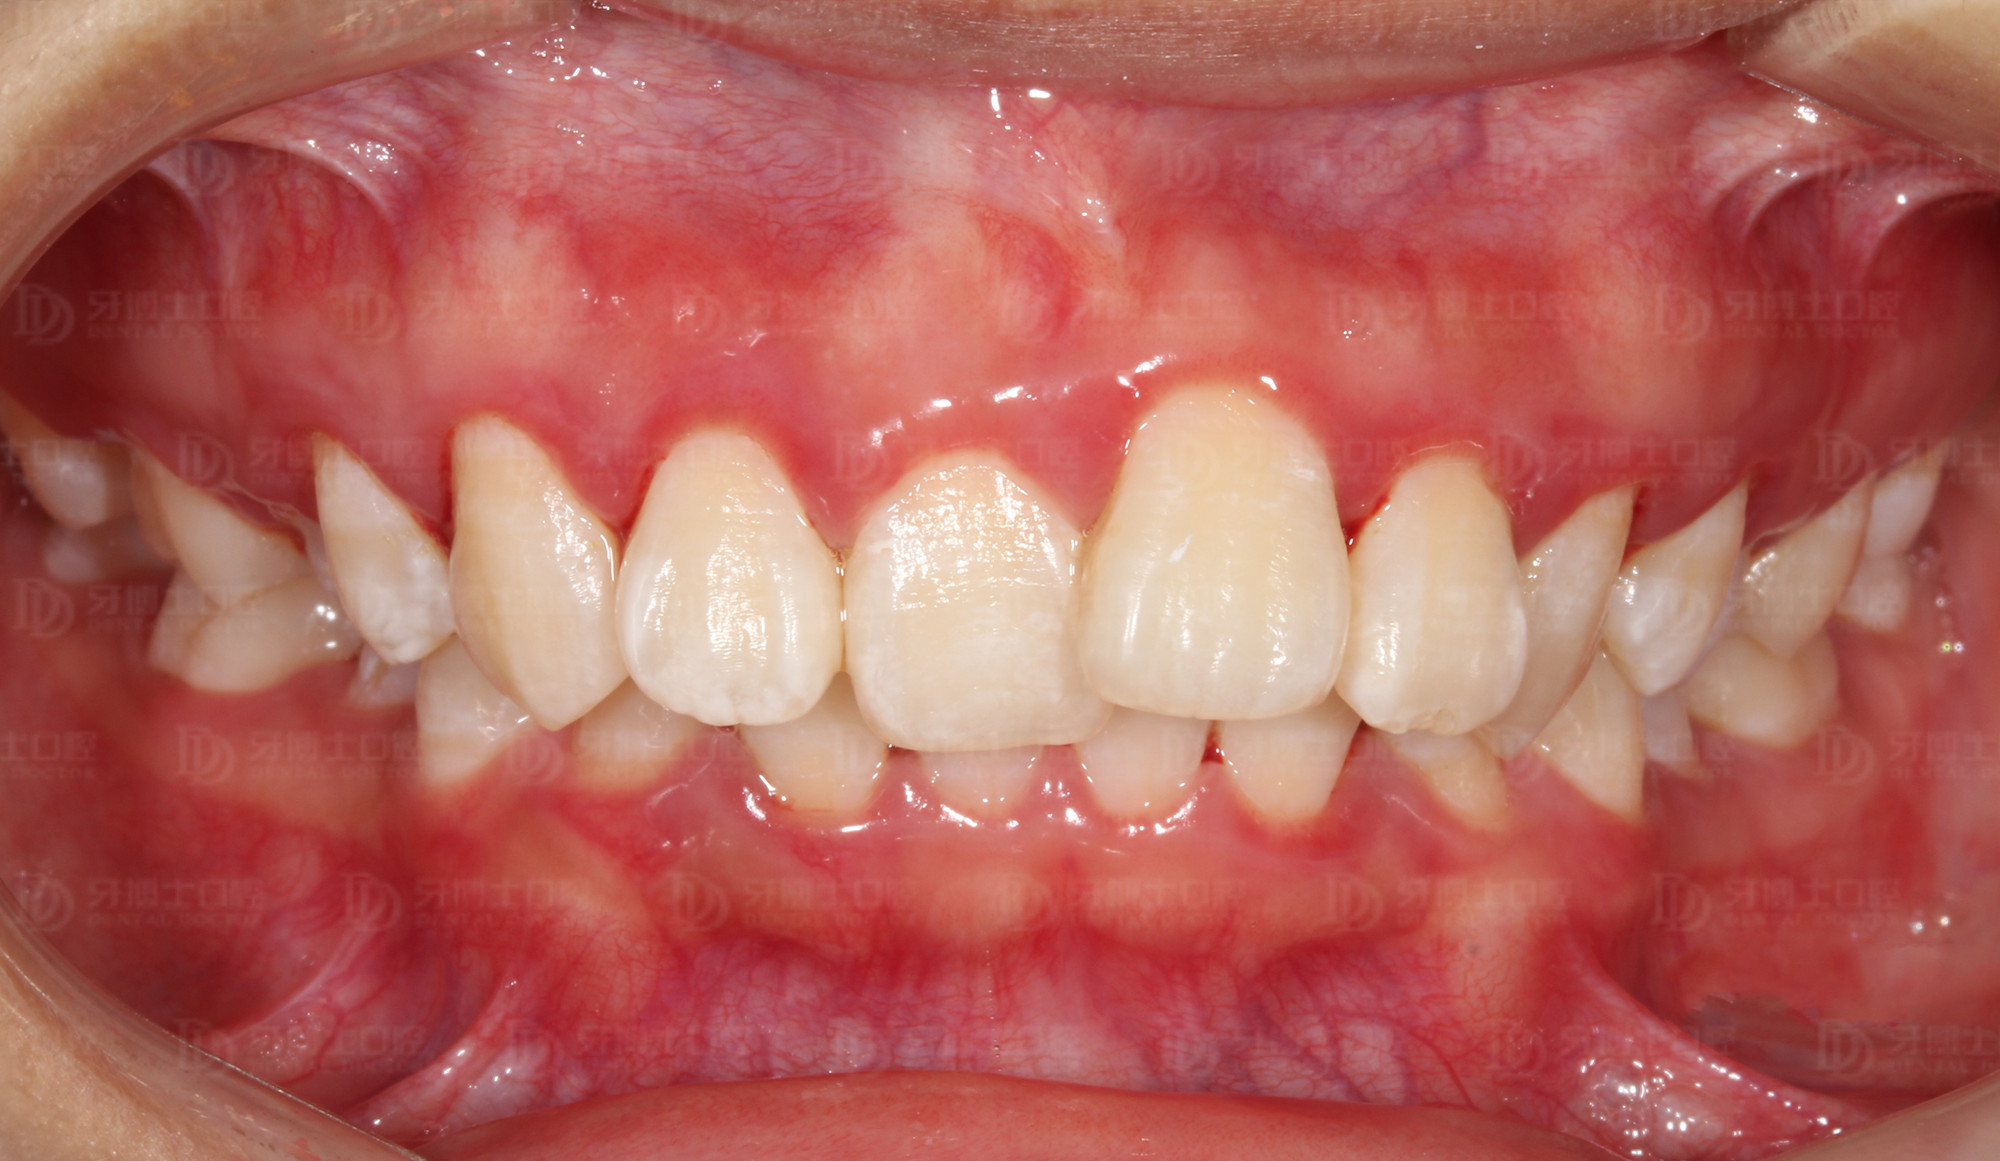

矫正前

牙列不齐,并有牙龈炎、牙结石,刷牙时会出血,同时美观度较差,影响容貌。